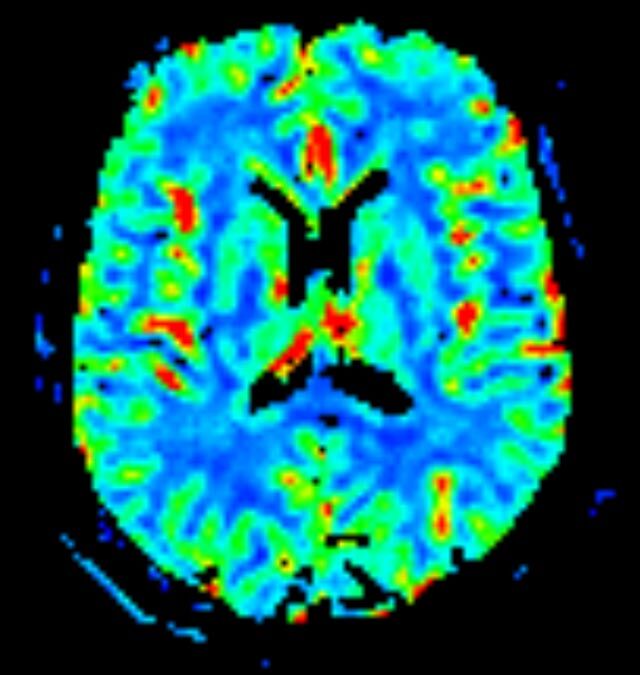

Kopf/Hals

• akute Schlaganfalldiagnostik und chronische Durchblutungsstörungen

• entzündliche Prozesse des Gehirns oder der Gesichtsweichteile

• Tumore

• Abklärung Schwindel, zentrale Sehstörung, Kopfschmerz

• Metastasenverdacht

• Multiple Sklerose

• Abklärung Hirnnerven, Schädelbasis inkl. Hypophyse

• Abklärung Kleinhirn, Hirnstamm, Halsmark

• intrakranielle Gefäße (Abklärung Verschluss, Stenose, Aneurysma)

• Halsgefäße zur Therapieplanung (z.B. Stent, Operation)

• Diffusionswichtung

• Perfusionswichtung

• Suszeptibilitätswichtung

• MR-Spektroskopie